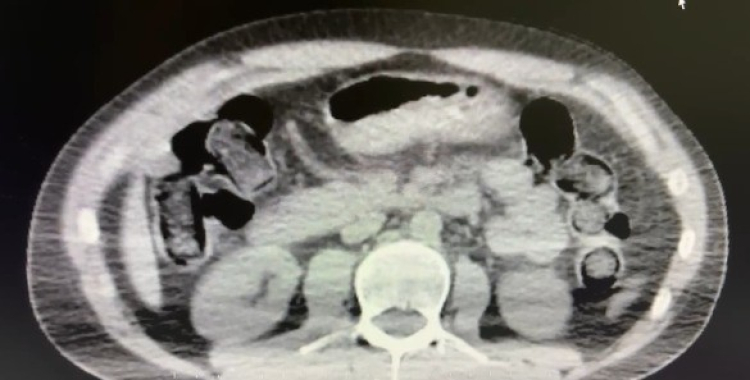

Nevşehir İl Emniyet Müdürlüğü Narkotik Suçlarla Mücadele Şube Müdürlüğü ekipleri, kentte uyuşturucu ve uyarıcı madde ticareti yapmak ve kullanmak suretiyle vatandaşları zehirleyen sokak satıcılarına yönelik çalışma başlattı. Cumhuriyet Başsavcılığı koordinesinde çalışmalarını yoğunlaştıran ekipler, şüpheliler S.B. ve O.R.'nin 'yutma yöntemi' ile kente uyuşturucu madde sevk edeceği bilgisi üzerine operasyon düzenledi. Şüphelilerin ikametlerinde ve araçlarında yapılan aramada 101 kapsül halinde 722 gram uyuşturucu madde, 1 adet hassas terazi, uyuşturucu madde sevkiyatında yutma yönteminde kullanılan muhtelif materyaller, uyuşturucu madde ticaretinden elde edilen 20 bin 210 TL, bin 320 euro ve 10 ABD doları ele geçirildi. Emniyetteki işlemlerinin ardından adliyeye sevk edilen 2 şüpheli, çıkarıldıkları mahkemece tutuklanarak cezaevine gönderildi.